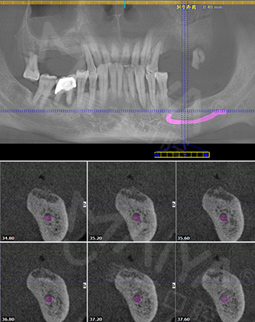

拍摄了CT,牙齿哪个地方有问题,看的很清楚,非常科学。但是口内有牙周病,需要先治疗再进行种牙,而且他们服务特别好,等待的时候还给倒水,安抚我让我感到很亲切,做了口内全口洁牙+喷砂+抛光+上药去除牙结石,是两个护士给洗的牙,一个细节就能提现这个机构好不好,卫生、环境方面都很不错,我也希望可以早点治疗好,做种植牙!